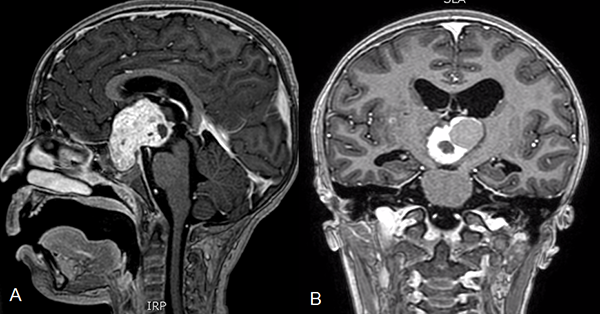

El tratamiento de los craneofaringiomas continúa planteando una controversia a lo largo del mundo.13La exéresis quirúrgica completa es el tratamiento ideal ya que permite mejor control de la enfermedad.14-16 Sin embargo, debido a la ubicación en la región selar y sus relaciones (el amplio contacto con el quiasma, el eje hipotálamo-hipofisario y las arterias del polígono de Willis), la exéresis completa sin producir daños a las estructuras circundantes es difícil de conseguir (figura 1).17-22

Figura 1. Resonancia magnética de cerebro con contraste. A y B. Corte sagital y coronal respectivamente donde se observa tumor sólido quístico en la región selar supraselar compatible con craneofaringioma.

En los últimos años, se fue instalando una tendencia a un mayor interés a preservar la calidad de vida de los niños y adolescentes con craneofaringiomas.31 El mejor tratamiento para los craneofaringiomas pediátricos ya no sólo involucra la resección completa de la lesión sino la preservación de la función endocrinológica.32 Estos tumores son de crecimiento lento y requieren de un tratamiento crónico, siendo importante recordar que en la población pediátrica la mayoría de los tumores son quísticos y de gran tamaño (más del 60% del volumen tumoral).5,11,32 A partir de esta premisa es que han surgido procedimientos menos invasivos como el uso del sistema de Ommaya, que provee alivio de los síntomas y permite retrasar la cirugía agresiva hasta la completa maduración del eje hipotálamo-hipofisario(figura 2).29

El tratamiento de craneofaringiomas mediante Ommaya ha pasado por diferentes estadios. Las primeras series trataban el quiste con Bleomicina,11,34 luego se intentó el tratamiento con Inteferón donde el equipo del SickChildren de Toronto presentó resultados muy alentadores,34 y por último la aspiración del quiste sin introducir ninguna sustancia.5 Drenar el quiste mediante el sistema de Ommaya es útil ya que permite que se reduzca el tamaño de la lesión y disminuye el contacto con las estructuras circundantes. Se encuentra descripto que luego de múltiples drenajes del quiste, la exéresis de la lesión es menos dificultosa debido a que presenta menos adherencias al hipotálamo, a la carótida interna o al quiasma.33 Otra ventaja del drenaje del quiste es que permite desbloquear los forámenes de Monro y mejorar la hidrocefalia obstructiva.3 Si bien nuestra serie de pacientes con Ommaya es muy reducida para sacar conclusiones definitivas, no encontramos un empeoramiento de las evaluaciones clínicas de los pacientes en el postoperatorio. Sin embargo, sólo 2 pacientes se mantuvieron estables luego del tratamiento, en los otros 5 casos se requirió de un tratamiento alternativo. Esto no debería considerarse como un mal resultado ya que la finalidad de la colocación del Ommaya no es curar la enfermedad sino retrasar los síntomas para permitirles a los pacientes una correcta maduración del eje (figura 3).

Figura 3. A. Resonancia cerebro corte sagital donde se observa tumor a predominio quístico en la región selar supraselar compatible con craneofaringioma. B. Tomografía de cerebro corte sagital postoperatoria de colocación de catéter intraquístico. C. Radiografía cráneo perfil donde se observa catéter radiopaco con extremo en la región selar.